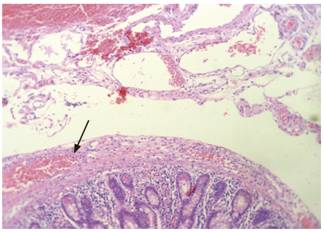

Con estos hallazgos se llevó a cirugía de emergencia para la realización de laparotomía exploratoria y se encontró una peritonitis de cuatro cuadrantes y un segmento de 10 cm de intestino delgado (yeyuno) de aspecto congestivo, edematoso y con áreas de necrosis, el cual se resecó. Se realizó anastomosis terminoterminal y lavado con solución salina tibia. El estudio del espécimen quirúrgico identificó la presencia de formaciones diverticulares con reacción inflamatoria (Figuras 3 y 4).

Sin embargo, existe otra forma de enfocar el dolor abdominal agudo en el paciente anciano y se basa en la probable causa etiológica que se puede resumir en causas obstructivas, inflamatorias, vasculares o criptogénicas 14, que por la edad y la presentación del caso están a favor de una condición inflamatoria frente a vascular (15. Finalmente, en este caso la patología logró identificar la presencia de enfermedad diverticular grave de yeyuno con signos de perforación (Figuras 3 y 4).